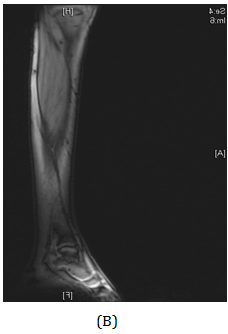

Figure 3 MRI of the lower limb showed aggressive bone lesion involving the distal diaphysis of the left fibula associated with huge soft tissue tumor.

A girl, 11yearsold Saudi presented to us with progressive swelling of the left lower limb, localized above the left ankle with complaints of pain and limping gait. She had visited many clinics for her pain and swelling with no relief to her symptoms. The patient was examined clinically and there was a swelling in the lateral aspect of the distal leg tender firm too hard with intact skin over it, 4x3 cm, no other systemic clinical finding of note. X-ray of the left leg (Figure 1) showed aggressive lytic lesion of the distal fibula. Thence patient was investigated with basic lab works plus systemic and local staging for further diagnosis. She was admitted under us in pediatric surgical ward for open biopsy of the distal fibular lesion and CT of the lower limb (Figure 2) showed destructive bone lesion involving the distal end of the fibula associated with extensive destruction and aggressive periosteal reaction associated with large soft tissue mass 4.5 x 5 cm in maximum axial dimension. Also, MRI of the lower limb (Figure 3) showed there is a large destructive bone lesion involving the distal diaphysis of the left fibula. This lesion does not cross the growth plate. It is associated with aggressive periosteal reaction along with a large soft tissue mass that appears of high signal intensity in T2 and intermediate to low signal intensity in T1 sequences. This was followed by technetium-99m MDP scintigraphy (Figure 4), it showed an increased tracer uptake in the distal left fibula, extending to the left ankle and the left foot. Excisional biopsy was taken from the proximal and distal margin of the lesion in the left fibula which confirmed Ewing's Sarcoma. According to the histopathology department, they reported that there is no evidence of residual tumor i.e free resection margins. (Figure 5) The patient was referred from us to pediatric oncology clinic for further evaluation. She was electively admitted to the hospital for staging and central line insertion to start chemotherapy. She treated as per Ewing sarcoma protocol in our hospital. Patient was put on neoadjuvant chemotherapy which included vincristine, cyclophosphamide, doxorubicin and etoposide, and if osfamide 3 times weekly. After 6 months of chemotherapy, we recommend to her family to do a surgery. We did a wide surgical resection of the tumor in the left leg. Subcutaneous tissue was dissected and isolation of superficial peroneal nerve was done. Dissection of lateral compartment of the left leg up to 16cm proximal to the lateral malleolus and distally, until the distal physis (Figure 6). The tendons of the peroneus longus, peroneus brevis, and flexor halluces longus were sacrificed and the ruminants were used to reconstruct for the lateral aspect of the left ankle using suture anchors (Figure 7). K-wires were used to do temporary arthrodesis (Figure 8). The surgical wound was closed in layers. VAC dressing was also applied as standard care management in Oncology cases at KFMC and backs lab was applied (Figure 9). The last MRI done for the patient showed there is altered signal intensity of the soft tissue with post-contrast enhancement. However, the dimensions of this area of altered signal intensity are decreased as compared to previous MRI. There is no evidence of soft tissue mass lesion (Figure 10). According to the last patient's follow up after six months post-operation it shows no Valgus deviation, normal ankle motion, mobilizing full weight bearing with splint assistant during physical examination (Figure 11). Also, X-rays and MRI finding shows no residual mass lesion or local recurrence.